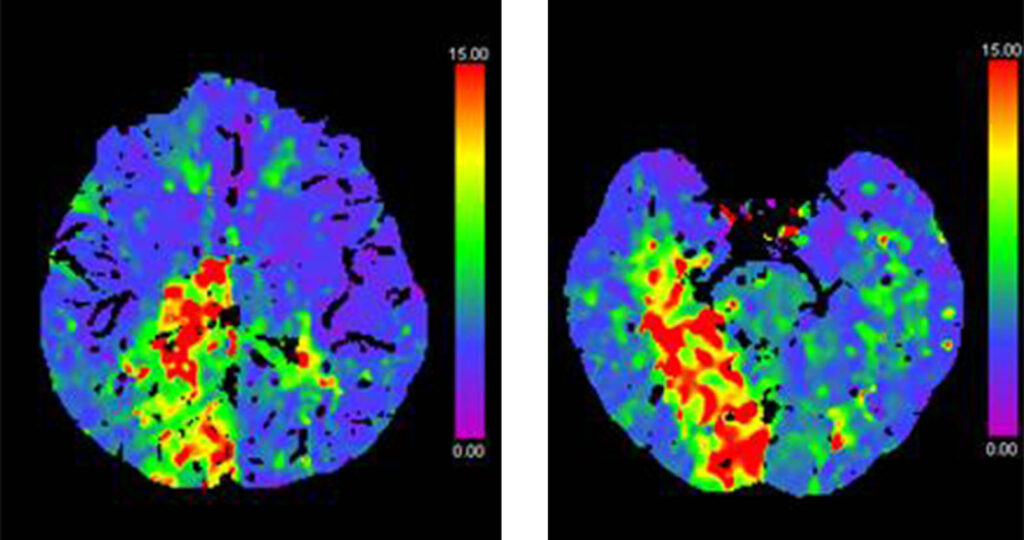

CT Perfusion maps (T-MAX) showing hypo-perfused posterior cerebral artery and AChA territories on the right side.